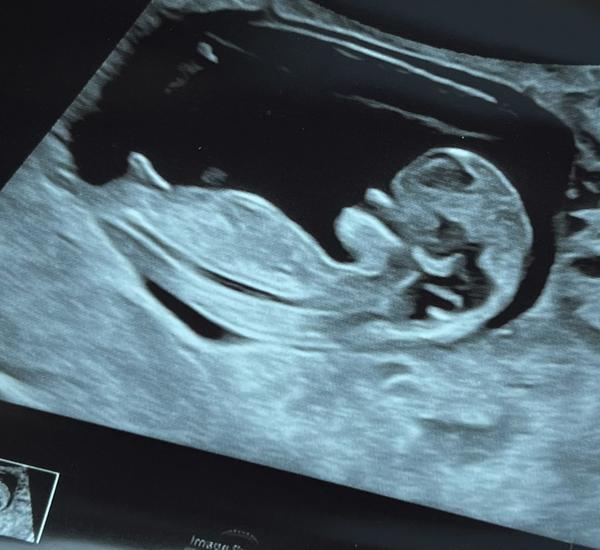

Dokážete odhadnout pohlaví miminka z ultrazvuku?

Ahoj holky, zřejmě dost častá diskuze a otázka. Ale zajímá mě názor “zkušených” rodiček, zda by si dokázaly tipnout na fotce z ultrazvuku pohlaví miminka i u mě? Jde mi jen o tipy, já pohlaví vědět nechtěla a teď jsem tak zvědavá, že se asi pana doktora při příští kontrole zeptám :D

Ale zase se přiznám, že jsem se minule tak na ultrazvuku (18tt) soustředila a žádný výběžek neviděla, každopádně to jsou opravdu jen moje hry s myšlenkami :D